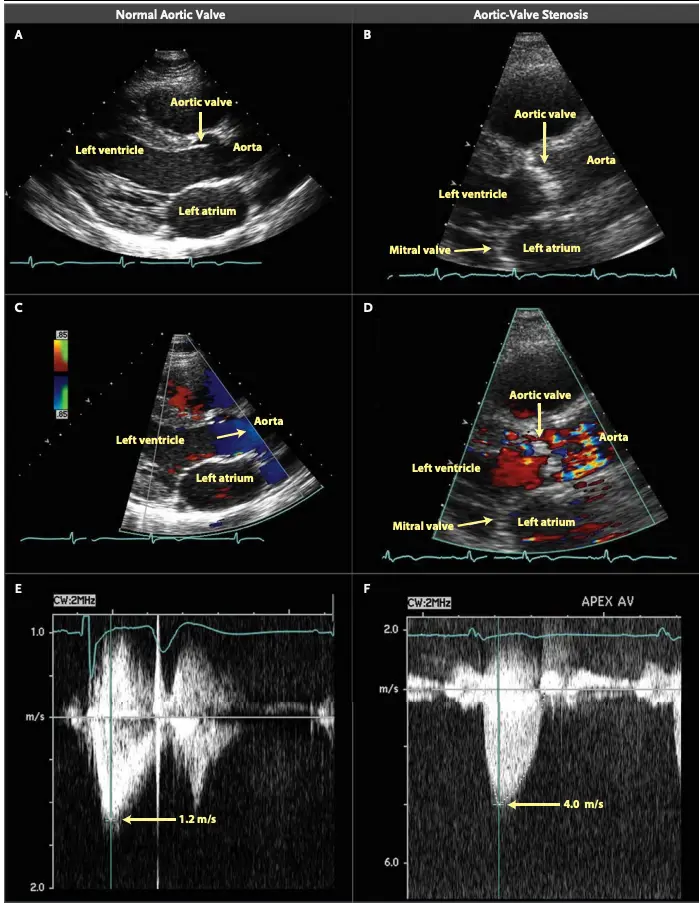

Echo for Valvular AS

Board Pearl: If normal Aortic Valve on 2D-echo and high gradient, think subvalvular AS, e.g. Subaortic Stenosis, or supravalvular AS.

- Cannot tell severity of stenosis with 2D-echo alone. You will need Doppler to help determine severity of AS.

- ==Valvular AS will be considered severe if mean gradient > 40 mmHg or peak velocity > 4 m/s (regardless of AVA)==

- Aortic velocity is measured using continuous-wave doppler ultrasound with examination from multiple acoustic windows

- Mean gradient is calculated by averaging instantaneous gradients over the systolic ejection period using the modified Bernoulli equation,

Underestimation due to improper Doppler alignment across the Aortic Valve

If not parallel to the AS jet, you will not get the highest mean AV gradient or peak velocity across the AV → underestimate severity of AS. Importantly, you cannot overestimate the gradient (Exceptions: significant anemia or Subaortic Stenosis).

- The above figure is from the Mayo Echo Boards video where the presenter highlights the importance of calculating the AV TVI in multiple windows to ensure you are appropriately calculating the highest VTI and avoid miscalculation/miscalssification. In Thaden et al (JASE, 2015), the authors found that peak velocity was found outside of the apical window 61% of the time and that neglecting non-apical window misclassified AS 23% of the time.